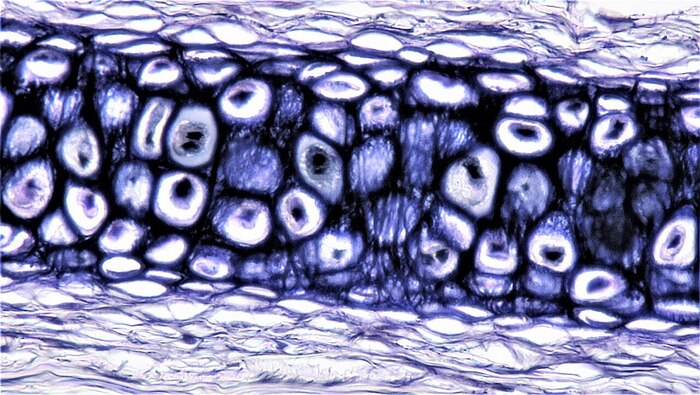

Un' iniezione che blocca una proteina chiave dell' invecchiamento ha permesso di rigenerare la cartilagine nelle articolazioni dei topi , invertendo la naturale perdita che avviene con l'età o a seguito di una lesione come quelle subite da atleti e sportivi. È il risultato ottenuto nella ricerca pubblicata sulla rivista Science e guidata dall'Università americana di Stanford, che ha sperimentato la terapia anche su tessuti umani provenienti da interventi di protesi del ginocchio. I risultati aprono nuove prospettive per il trattamento di artrite e traumi che eviterebbero le protesi di anca e ginocchio ed è già in fase di sperimentazione anche una terapia per via orale.

I ricercatori coordinati da Helen Blau e Nidhi Bhutani si sono concentrati su una proteina nota con la sigla 15-pgdh , nota per il ruolo che riveste dell'invecchiamento. Precedenti studi dello stesso gruppo avevano mostrato che inibire l'attività di questa proteina favorisce la rigenerazione di molti tessuti , dai muscoli ai nervi, dalle ossa alle cellule del sangue, ma non era ancora chiaro se lo stesso valesse per la cartilagine delle articolazioni.

Gli autori dello studio hanno quindi sperimentato su topi l'iniezione di un farmaco che blocca la proteina 15-pgdh , prima nell'addome e poi direttamente nell'articolazione interessata. In entrambi i casi, la cartilagine danneggiata e assottigliata degli animali anziani si è ispessita e rigenerata . Risultati simili sono stati osservati in topi con lesioni al ginocchio che si verificano frequentemente nelle persone che fanno molto sport: iniezioni fatte due volte a settimana per quattro settimane hanno ridotto drasticamente la probabilità di sviluppare osteoartrite, una condizione molto comune in questi casi.